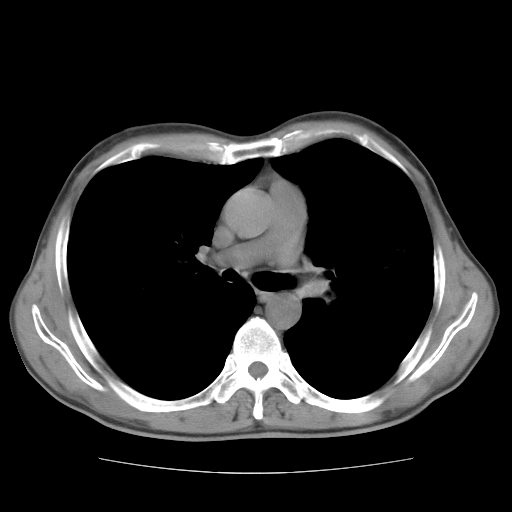

以下是引用drzhang8888在2008-11-20 22:20:00的发言:[br]密集的短毛刺,血管集束,胸膜凹陷,周边型肺癌可能性大,另双肺多发磨玻璃影,考虑感染

以下是引用流浪星在2008-11-20 22:28:00的发言:[br]左肺上叶近外围区见一类圆形结节影,毛刺征、胸膜尾征阳性,临近肺组织见多发渗出灶。考虑1,炎症性病变。 2.周围性肺癌。建议抗炎治疗后复查。

以下是引用qc80012345在2008-11-21 5:53:00的发言:[br]支持;周围型肺癌诊断。增强扫描。